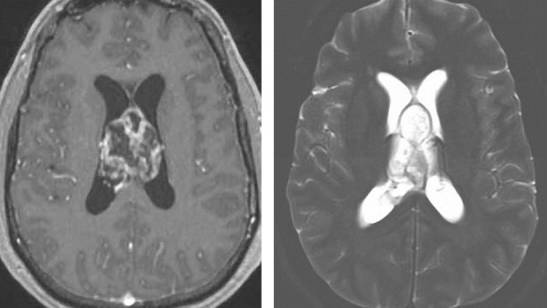

图5. 髓母细胞瘤在T1相上相对白质呈低信号,往往呈不均匀强化。在T2相上,由于钙化、坏死和囊性变的存在往往表现为混杂信号。

图6. 高级别胶质瘤具有不规则的边界和结节,呈不均匀的强化表现。在T2相上表现为高信号。位于透明隔的肿瘤与神经细胞瘤相似。